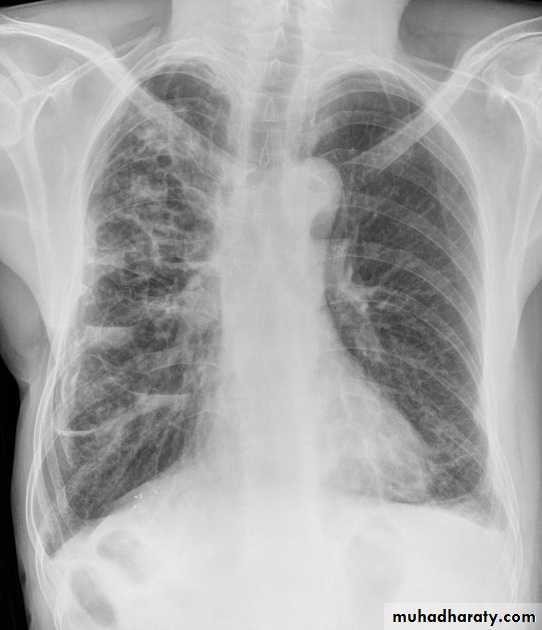

Secondary metastasis

74.secondary metastasis to the lung ( canon ball appearance )